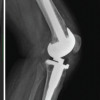

Patient 1 is a 78-year-old male who underwent a primary left TKA on February 10, 2022, with no complications. Pre-operative X-rays confirmed the presence of osteoarthritis and joint space narrowing (Fig. 1, Top Left).

Postoperatively, the patient participated in outpatient physical therapy 2–3 times per week for 9 weeks, beginning 4-day postoperatively. During physical therapy, a decline in peak ROM was noted at 4 weeks. X-rays taken at this time confirmed proper joint alignment and well-affixed implants (Fig. 1, Top Right). The patient’s medical history includes high cholesterol and sleep apnea, as well as hearing loss and frequent urination. The patient was a former smoker, who ceased over 16 years ago and self-reports a moderate level of alcohol consumption. Preoperatively, the patient had a limited peak ROM of 5–95°. During the first 2 weeks following surgery, the patient averaged a functional ROM of 42°. The recovery curve for this parameter shows that the patient was below the 25th percentile, among men ≥65 years. Peak ROM was 4–83° at 2-weeks post-TKA. Functional ROM averaged 43.5° over weeks 3 and 4, followed by a decrease at week 5, illustrated on the recovery curve as the patient’s functional ROM falling below the 5th percentile. 7-week post-TKA, the peak ROM had increased to 3-115° but the functional ROM was only at the 10th percentile. Although the patient had made progress in their peak knee flexion, they were still unable to reach full extension of the knee, and the patient reported increased pain and swelling. For these reasons, an MUA was performed 9 weeks following surgery. Following the MUA, physical therapy was prescribed 5 times per week for 2 weeks, followed by an additional 2–3 times per week for 6 weeks. Three weeks following MUA, functional ROM increased to an average of 48.5°, while peak ROM was 11–99°. By 7-week post-MUA, approximately 16 weeks after initial TKA, the patient had a functional ROM of 50.3°, and peak ROM was measured at 6–111°. Over the next 4 weeks, the patient averaged 52° of functional ROM (Fig. 2, Top). Patient two is a 34-year-old female who underwent a primary left TKA on June 1, 2022 with no complications. Pre-operative X-rays confirmed severe osteoarthritis and joint space narrowing (Fig. 1, Middle Left). The patient participated in outpatient physical therapy 1–3 times per week for 6 weeks starting 2 days after surgery. Post-operative X-rays confirmed proper joint alignment and well-affixed implants (Fig. 1, Middle Right). The patient’s past medical history consists of a previous ACL and meniscal repair, hypothyroidism, arthritis, and Type 2 diabetes. This patient does not have a history of smoking and self-reports occasional alcohol consumption.